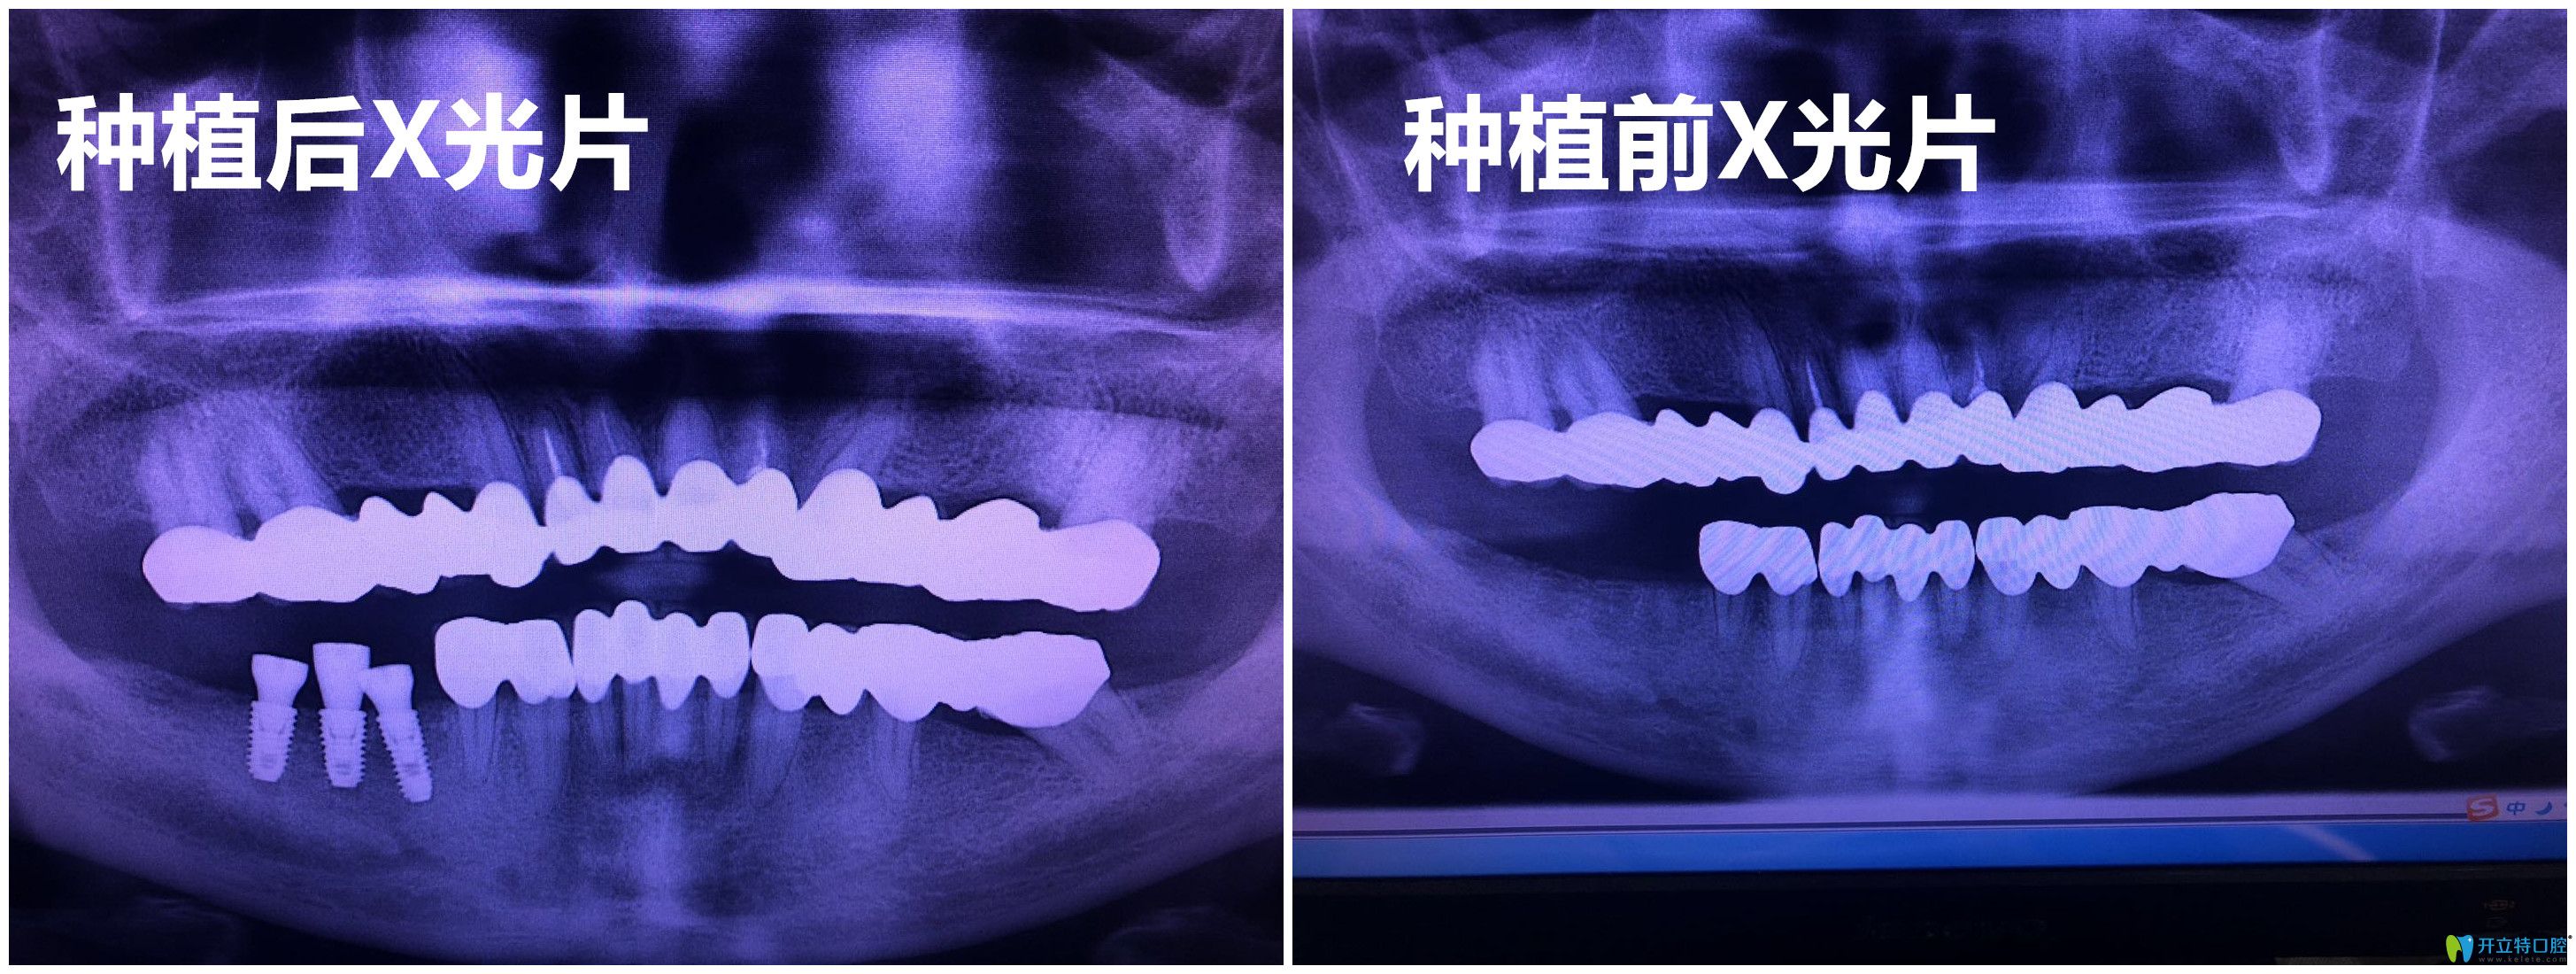

杭州逸盛口腔謝精文種植牙案例:

種植前:牙齒缺失三顆,平時吃東西特別不方便

種植后:在吃東西的時候沒有異物感,而且?guī)缀鯖]有什么需要忌口的,感覺和牙齒缺失時候沒有什么兩樣。

杭州逸盛口腔謝精文種植牙案例